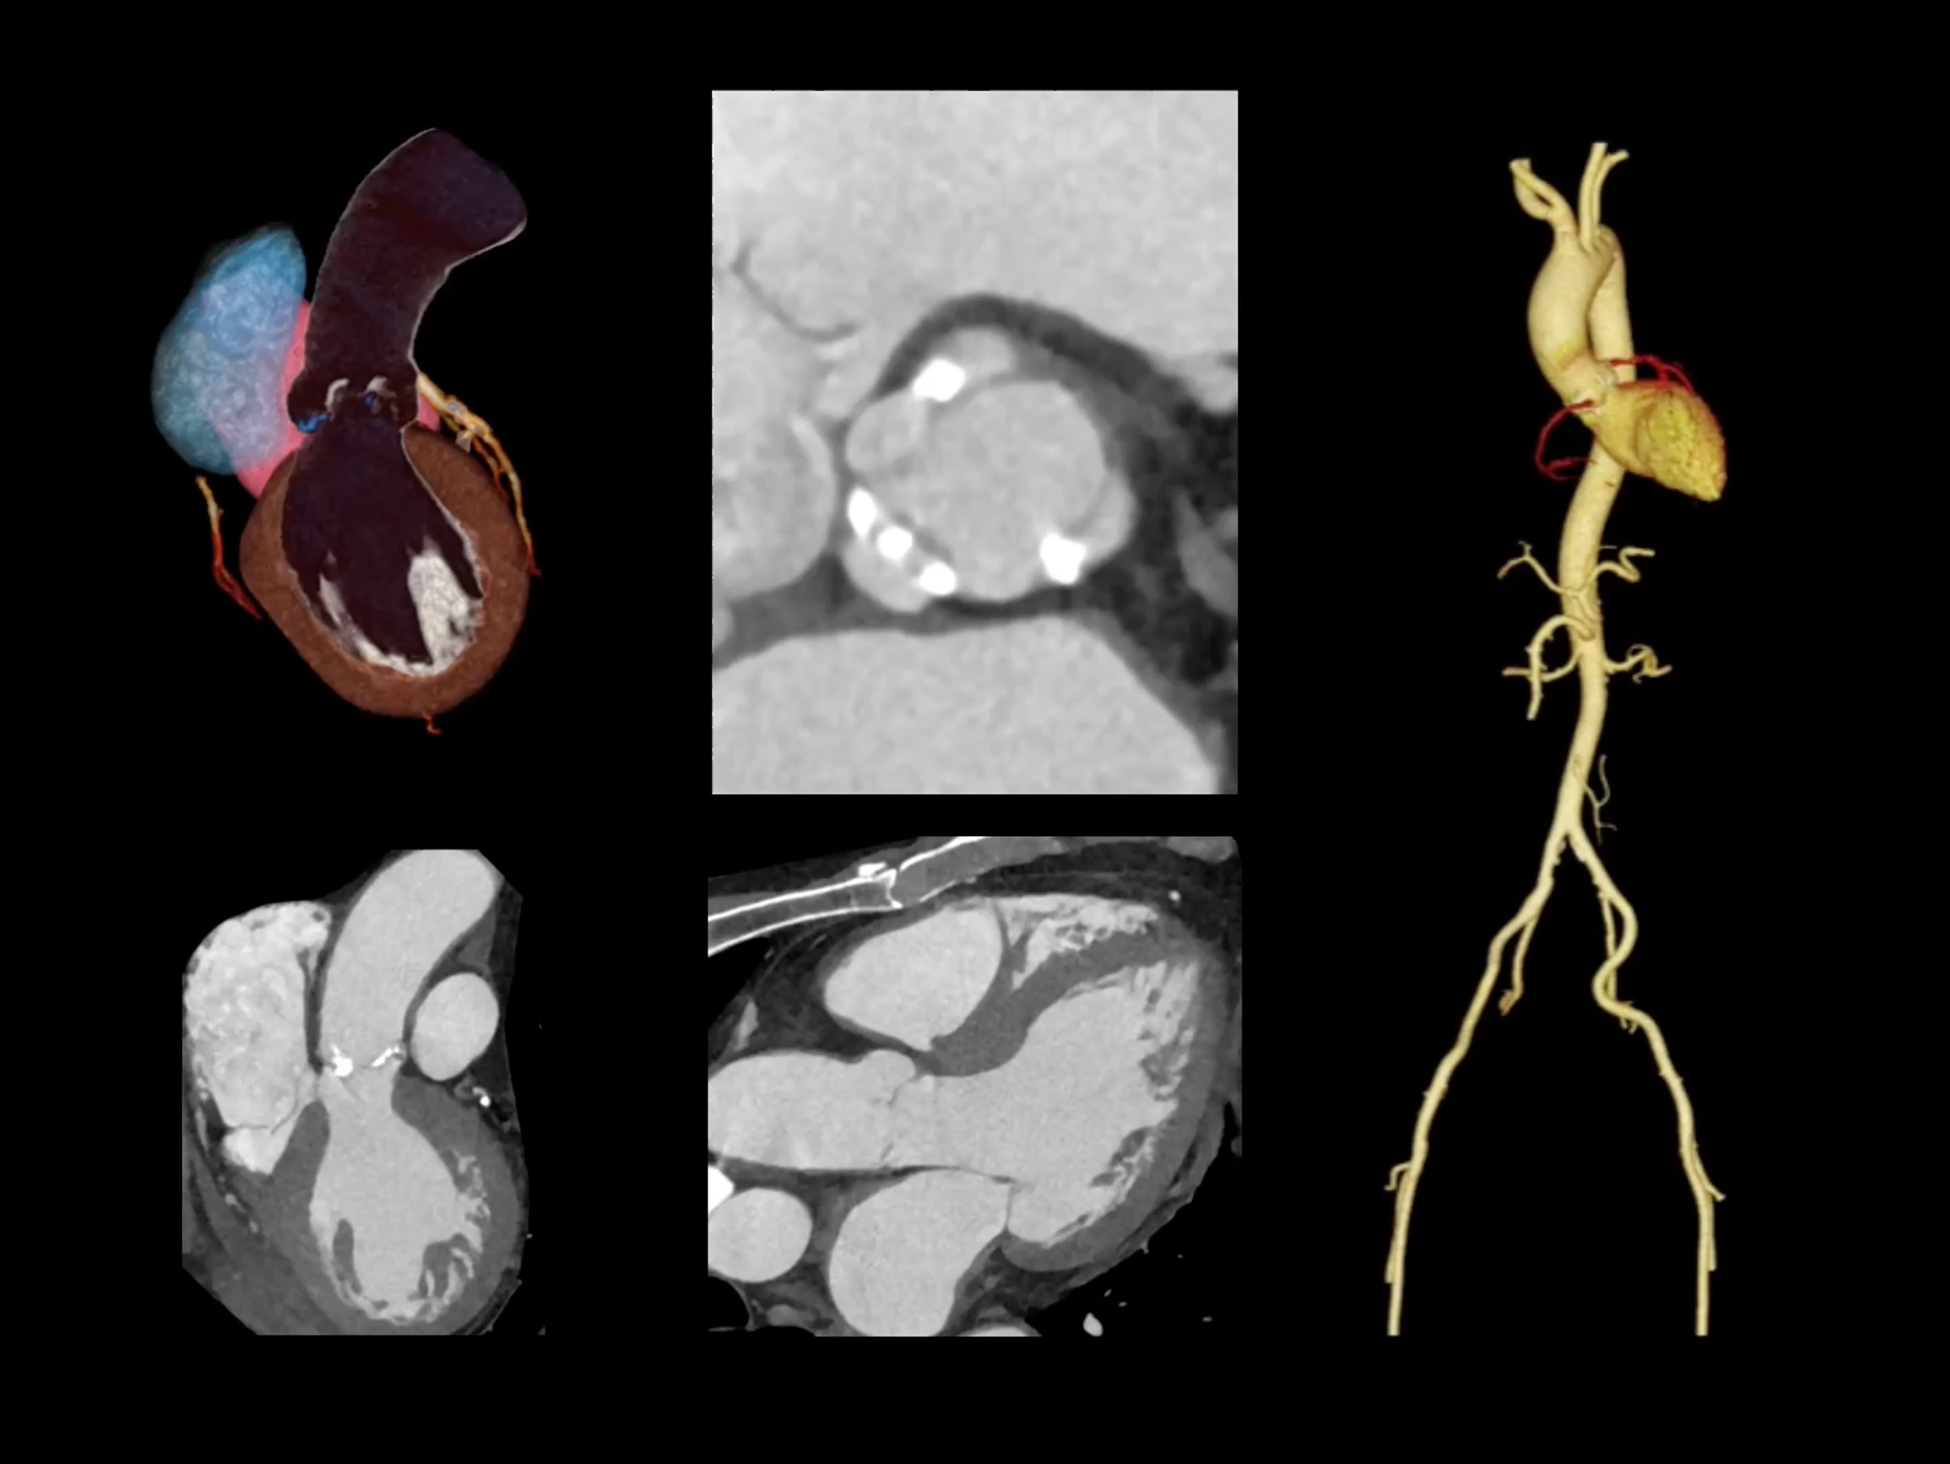

全身各部位动态CT成像

全时心脏

uCT SiriuX® 挑战心脏成像时间分辨率的极限,精准捕捉心脏全周期的动态变化。无论静态解剖形态,还是动态功能表现,都能清晰呈现,让心脏不再是“定格”的器官,而成为可视的生命律动。

心脏成像,自由掌控

uCT SiriuX® 以 8ms 全心等效时间分辨率与16cm宽体覆盖,突破传统心脏成像局限,完整呈现搏动中的心脏结构与动态功能;配合无心电门控扫描与智能化工作流,更使心脏检查摆脱心率、配合度与操作复杂度的束缚,实现真正自由从容的成像体验,为临床功能评估提供更深层依据。

全心4D电影成像

提供全心动周期内多个时相的清晰结构成像信息,动态展示心脏结构运动变化。

全心全时相高清成像

单心动周期内的任意时相获取高质量的冠脉CTA图像,确保稳定的心脏成像效果。

单时相无心电冠脉成像

在更短单时相曝光下,实现自由呼吸、无门控的冠脉CTA成像,以低剂量、无门槛的方式,重塑心脏扫描体验。

一站式心脏多维成像

一次对比剂注射可同时获取冠脉CTA、心肌灌注和心肌延迟强化等多维图像信息。